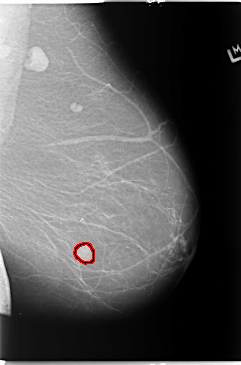

B_3102_1.LEFT_CC

FILE: B_3102_1.LEFT_CC.OVERLAY

TOTAL_ABNORMALITIES 1

ABNORMALITY 1

LESION_TYPE MASS SHAPE OVAL MARGINS CIRCUMSCRIBED

ASSESSMENT 4

SUBTLETY 5

PATHOLOGY BENIGN

TOTAL_OUTLINES 1

BOUNDARY